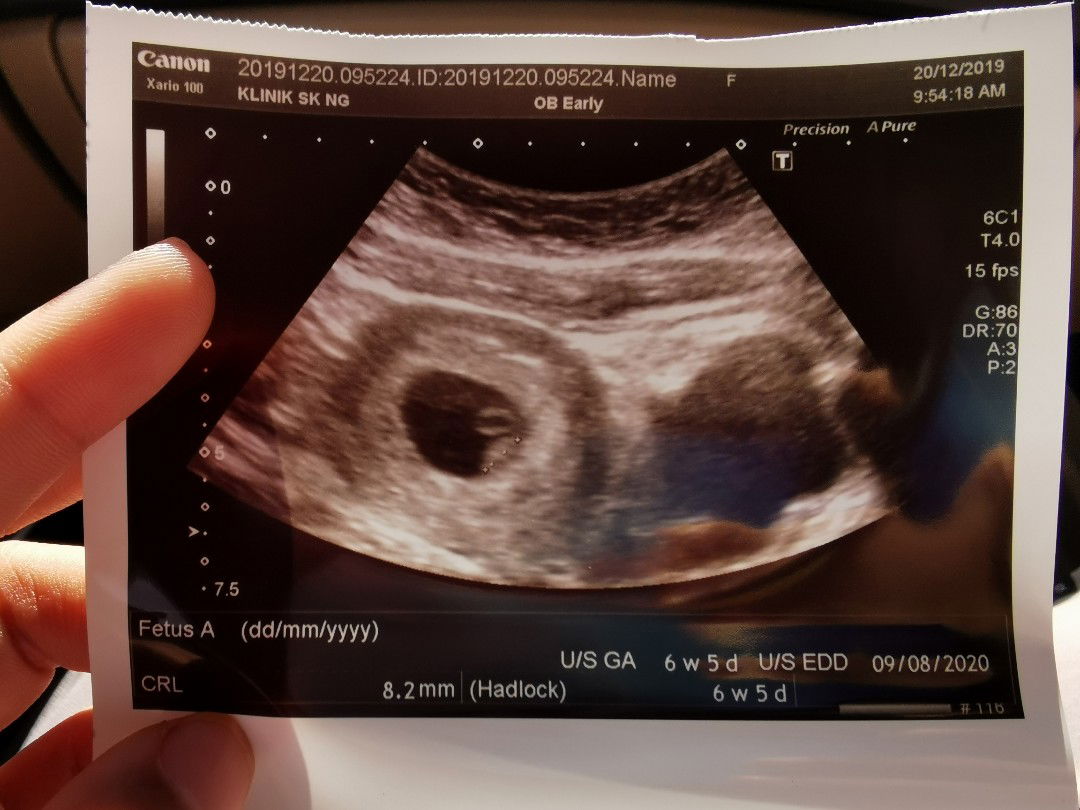

Ya Allah.. mcm xpercaya dapat dengar jantung anak sendiri.. penantian 7tahun ku. Moga Allah sentiasa jaga dia dan membesar dgn sihat dalam rahimku ini. Doakan sy ye mommies2 sekalian. semoga baby selamat hingga melahirkan.